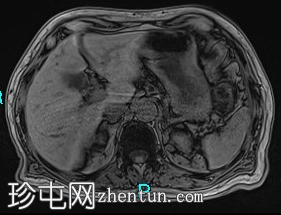

MRI

冠状位

T2加权像

胰腺钩突附近可见边界不清的肿块,T2加权像呈不均匀中等信号,弥散受限明显。肿块大小为4.1 x 5 x 3 cm(前后径 x 横径 x 头尾径)。伴有胰管扩张,直径约6 mm。

肝脏可见多个大小不一的可疑病灶(从亚厘米级到2厘米不等)。T2加权像呈高信号,弥散受限明显。

远端胆总管突然变窄,但未完全阻塞。

胰腺周围可见多发囊性病变,部分与主胰管相连,提示胰腺导管内乳头状黏液性肿瘤(IPMN)。

双侧胸腔积液,左侧较多。